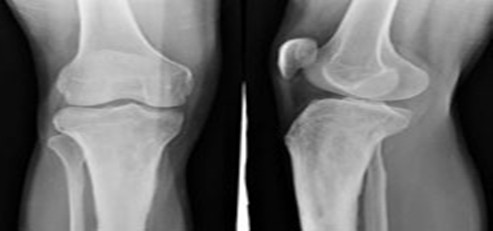

济南中德骨科医院骨创伤诊疗中心是医院的重点科室之一,科室以骨创伤外科为基础,拥有专业的医疗设备和技术娴熟的医疗团队,经过发展科室逐渐形成了以复杂手外伤,骨折、断肢(指)再植、四肢血管神经损伤修复、组织缺损移植修复、四肢复杂骨折的处理和治疗为主的特殊专科。

诊治范围:手足部急诊外科修复、断掌、断肢再植,足趾再植,断指再植(多指离断、手指多段离断、小儿手指离断等),拇手指缺损再造,上肢骨损伤、血管、周围神经及肌腱损伤的修复,手及四肢软组织缺损的各种皮瓣修复,手足畸形矫治。